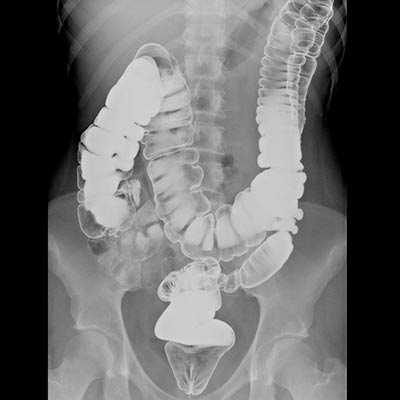

(Слева) На рентгенограмме, полученной во время исследования пассажа бариевой взвеси по тонкой кишке, определяется стриктура терминальных отделов подвздошной кишки в виде «огрызка яблока» с сужением просвета, деструкцией слизистой оболочки и подрытыми краями. Эти изменения являются классическими признаками первичного рака тонкой кишки.

(Справа) На рентгенограмме, выполненной во время исследования пассажа контраста по тонкой кишке, визуализируется объемное образование В тощей кишки с наличием характерных признаков первичного рака тонкой кишки: узловидно утолщенных складок, деструкции слизистой оболочки и сужения просвета. Определяется дилатация отделов кишечника, расположенных выше уровня опухоли.